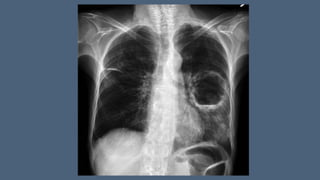

• chest X-ray (a chest radiograph usually detects a thick-walled cavity with an air-

f

luid level,)

• CT Chest (CT may also yield additional information regarding a possible underlying cause of

lung abscess, such as malignancy, and may help distinguish a peripheral lung abscess from a

pleural infection.)